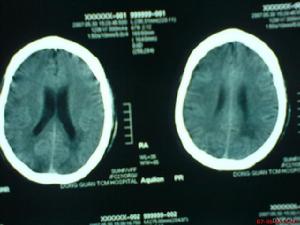

4、顱腦CT可見腦內大小不等、邊界不清的低密度灶。

5、放射學檢查:常規頭顱放射學檢查對散發性腦炎的診斷無重要價值。頭顱CT有時可見大腦半球多個散在的軟化灶,對排除占位性病變有一定意義。